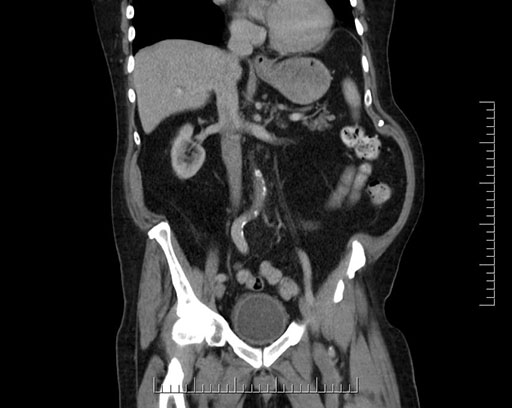

Coronal - stented